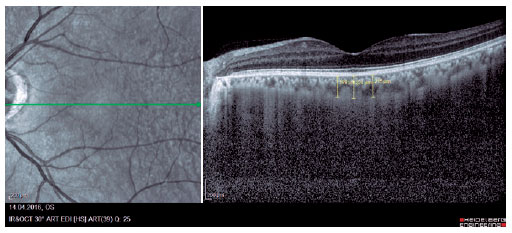

We retrospectively evaluated 32 obese patients with BMI of >30 kg/m2 who presented at the Internal Medicine Polyclinic due to obesity and who were also evaluated at the Ocular Diseases Polyclinic between January 2016 and June 2017 and 45 healthy control individuals. Eye IOP and OPA values of patients measured using Pascal DCT (Ziemer Group, Switzerland) and CT measured using enhanced depth imaging (centralized fovea for choroildal imaging) OCT (85,000 Hz OCT2 Next Generation SPECTRALIS OCT, Heidelberg Engineering) were assessed. These values were measured by the same physician and at the same time of the day. Only the most reliable measurements with scores 1 and 2 were included in the study. CT was manually measured by a single ophthalmologist based on the external boundary of retinal pigment epithelium and that of the choroidal vascular bed. It was measured three times at the subfoveal, nasal, and temporal regions at a distance of 500 µm from the macula, and the average of these three measurements was used for analyses (Figures 1-3). IR was assessed using the homeostasis model assessment-estimated IR (HOMA-IR) index(9), which was calculated as follows: HOMA-IR=[fasting plasma insulin (mIU/mL) × fasting plasma glucose (mmol/L)]/ 22.5(10). HOMA-IR index of 2.5 was set as the cutoff value(11). Patients with ocular tension and corneal disease, those with nonobesity systemic diseases, those who underwent eye surgery, and those who underwent interventions such as laser therapy and intravitreal injections were excluded from the study. This study was approved by the Ethics Committee of the Adiyaman University (#2017/7-19).